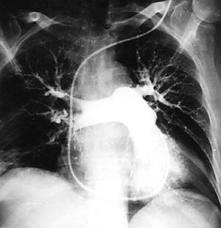

Для установления диагноза необходим осмотр больного, проведение исследований, включающих: ЭКГ, ЭхоКГ, D- димер (является продуктом деградации фибрина, его плазменный уровень повышается при тромбообразовании), рентгенографию грудной клетки, КТ-ангиографию грудной клетки, вентиляционно-перфузионную сцинтиграфию легких (исследование сосудов легких с помощью контрастных веществ для определения объема поражения). Ультразвуковое ангиосканирование вен нижних конечностей дает возможность обнаружить источник эмболизации. Комплексное рентгеноконтрастное исследование, включающее зондирование правых отделов сердца, ангиопульмонографию и ретроградную илеокавографию, остается "золотым стандартом" и позволяет однозначно решить все диагностические проблемы при подозрении на ТЭЛА.